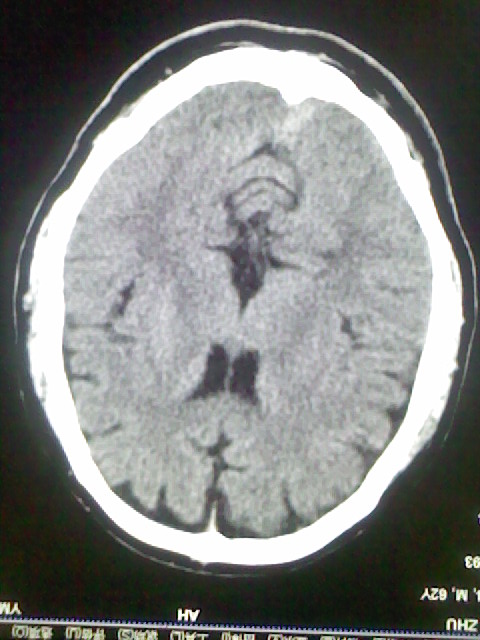

标题: CT15555:头痛 10余日 来诊大家帮忙看看 [打印本页]

标题: CT15555:头痛 10余日 来诊大家帮忙看看

脑萎缩

脑沟、裂增宽,提法脑萎缩,建议mt检查。

脑萎缩,以小脑为著。

脑沟、裂增宽,提示脑萎缩

老年脑

支持轻度脑萎缩。